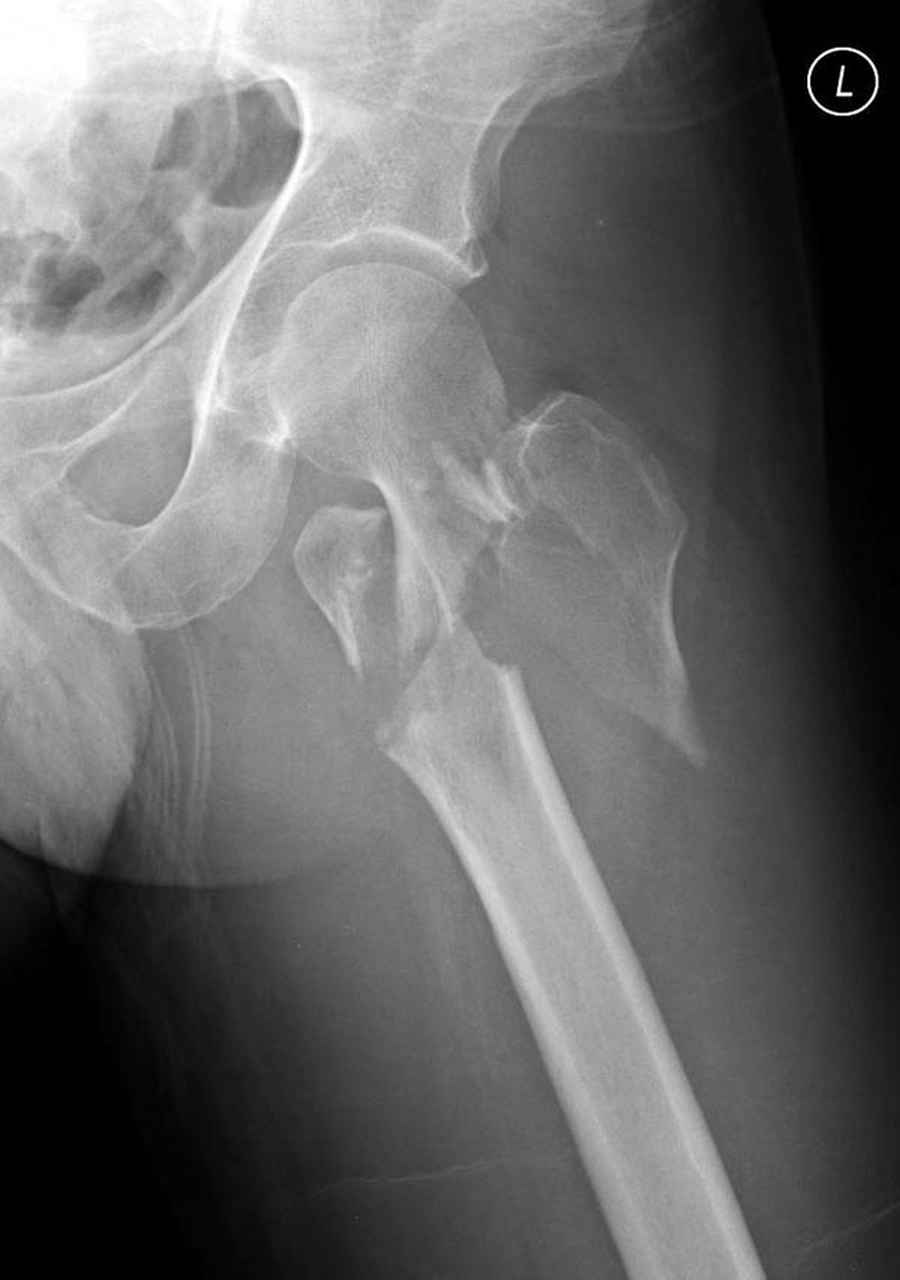

Re: Чрезвертельный перелом бедра

Предлагаемое как вариант консервативное лечение чрезвертельных переломов существует, но это суровое наказание для больного и возврат к прошлому. Такой метод можно предложить, когда невозможно сделать операцию из-за соматического состояния при большом риске от вмешательства.

Из фиксаторов, мы бы применили цефаломедуллярные, потому что они "по закону моментов" из-за короткого рычага от центра головки к диафизу и по принципу "головка диафиз" механически лучше выдерживают нагрузки, чем пластины.

Здесь пара случаев фиксации похожих переломов:

первый высокоэнергетическая травма 36 лет